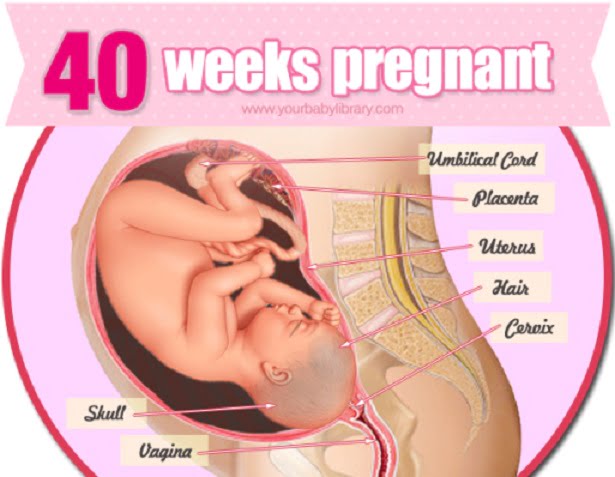

هفته چهلم (38 هفته بعد از لقاح)

اندازه جنین:

طول 35 تا 40 سانتیمتر

وزن: حدود سه کیلوگرم

نقطه عطف رشد جنین: روز تولد

فرزند شما در هفته چهلم بارداری

حالا کودکتان چاق شده است. 15% بدن کودک از چربی تشکیل شده که به تنظیم دمای بدنش کمک میکند. اگر کودکی با سایز متوسط باشد احتمالا وزنی بین 7 تا 8 پوند و 21 اینچ طول دارد. اکثر موهای بدنش ناپدید شده اند اما هنوز هم یک لباس غواصی طبیعی به تن دارد – لایه نازکی از مواد چرب سفید که ونیکس کاسه اوسا نام دارد و به ایجاد حفاظت بیشتر از پوست کودک در مقابل اولین هوای سرد کمک میکند.

باشد متوجه میشوید که سر نوزاد شما به سمت لگن شماست (در صورتیکه او برعکس نباشد و با وضعیت بریچ متولد

نشود که در این حالت ممکن است پزشکتان پیشنهاد سزارین بدهد). بدن کودکتان نیز راست و بالا به پایین است

که طولی نامیده میشود و ممکن است بدن او در زاویه قرار گرفته باشد که مورب نامیده میشود. همزمان با

بیان موقعیت کودکتان اگر بتوانید سرش را پیدا کنید متوجه میشوید که سر پایین و روبروی ستون فقرات

شماست که معمولترین موقعیت است (که روبه جلو نامیده میشود). اما گاهی کودک سر پایین است

اما صورتش روبروی شکم است. این وضعیت پشت گردنی یا پشت جمجمه نامیده میشود.